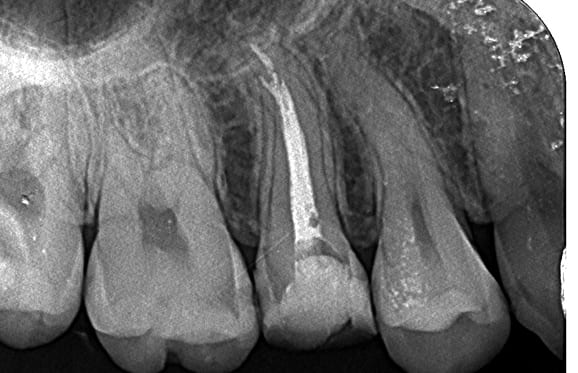

根管内の破損器具除去

● 症例1

01 左下7の近心根にエンジンファイルの破折

02 ファイル除去時

※根尖周囲の透過像はまだ残存

03 最終の根充剤を充填

※根尖透過像が小さく治癒方向へ向かっている